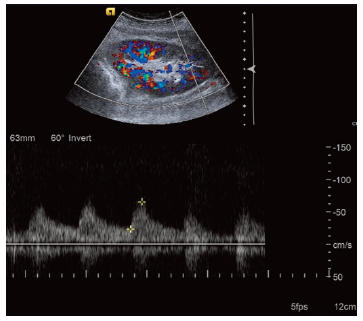

The cause of chronic kidney disease (CKD) in 9 of 38 kidney recipients was hypertension. The other etiologies were vesicoureteral reflux (n = 5), type 2 diabetes mellitus (n = 4), unknown (n = 3), polycystic kidney disease (n = 2), focal segmental glomerulosclerosis (n = 2), membranoproliferative glomerulonephritis (n = 2), nephronophthisis (n = 2), cystinosis (n = 2), and other (gout, oxalosis, nephrotic syndrome, Fabry disease, immunoglobulin A nephropathy, drug-induced nephrotoxicity, neuro­genic bladder) (n = 6). All recipients were treated in a COVID-19 transplant facility after transplant surgery. Doppler ultrasonography was performed on kidney recipients on days 3 and 5 after transplant surgery, and all results were completely normal (Figure 1). The average length of hospital stay was 8.1 days (range, 3-18 days) (Table 1). Mean serum creatinine values of the KT recipients were 0.91 mg/dL at post-operative day 7, 0.86 mg/dL at day 30, and 0.74 mg/dL at day 90 (Figure 2). Mean glomerular filtration rates were 77.2 mL/min/1.73 m2 at post-operative day 7, 82.4 mL/min/1.73 m2 at day 30, and 88 mL/min/1.73 m2 at day 90 (Figure 3). All KT recipients were discharged successfully with normal kidney functions.